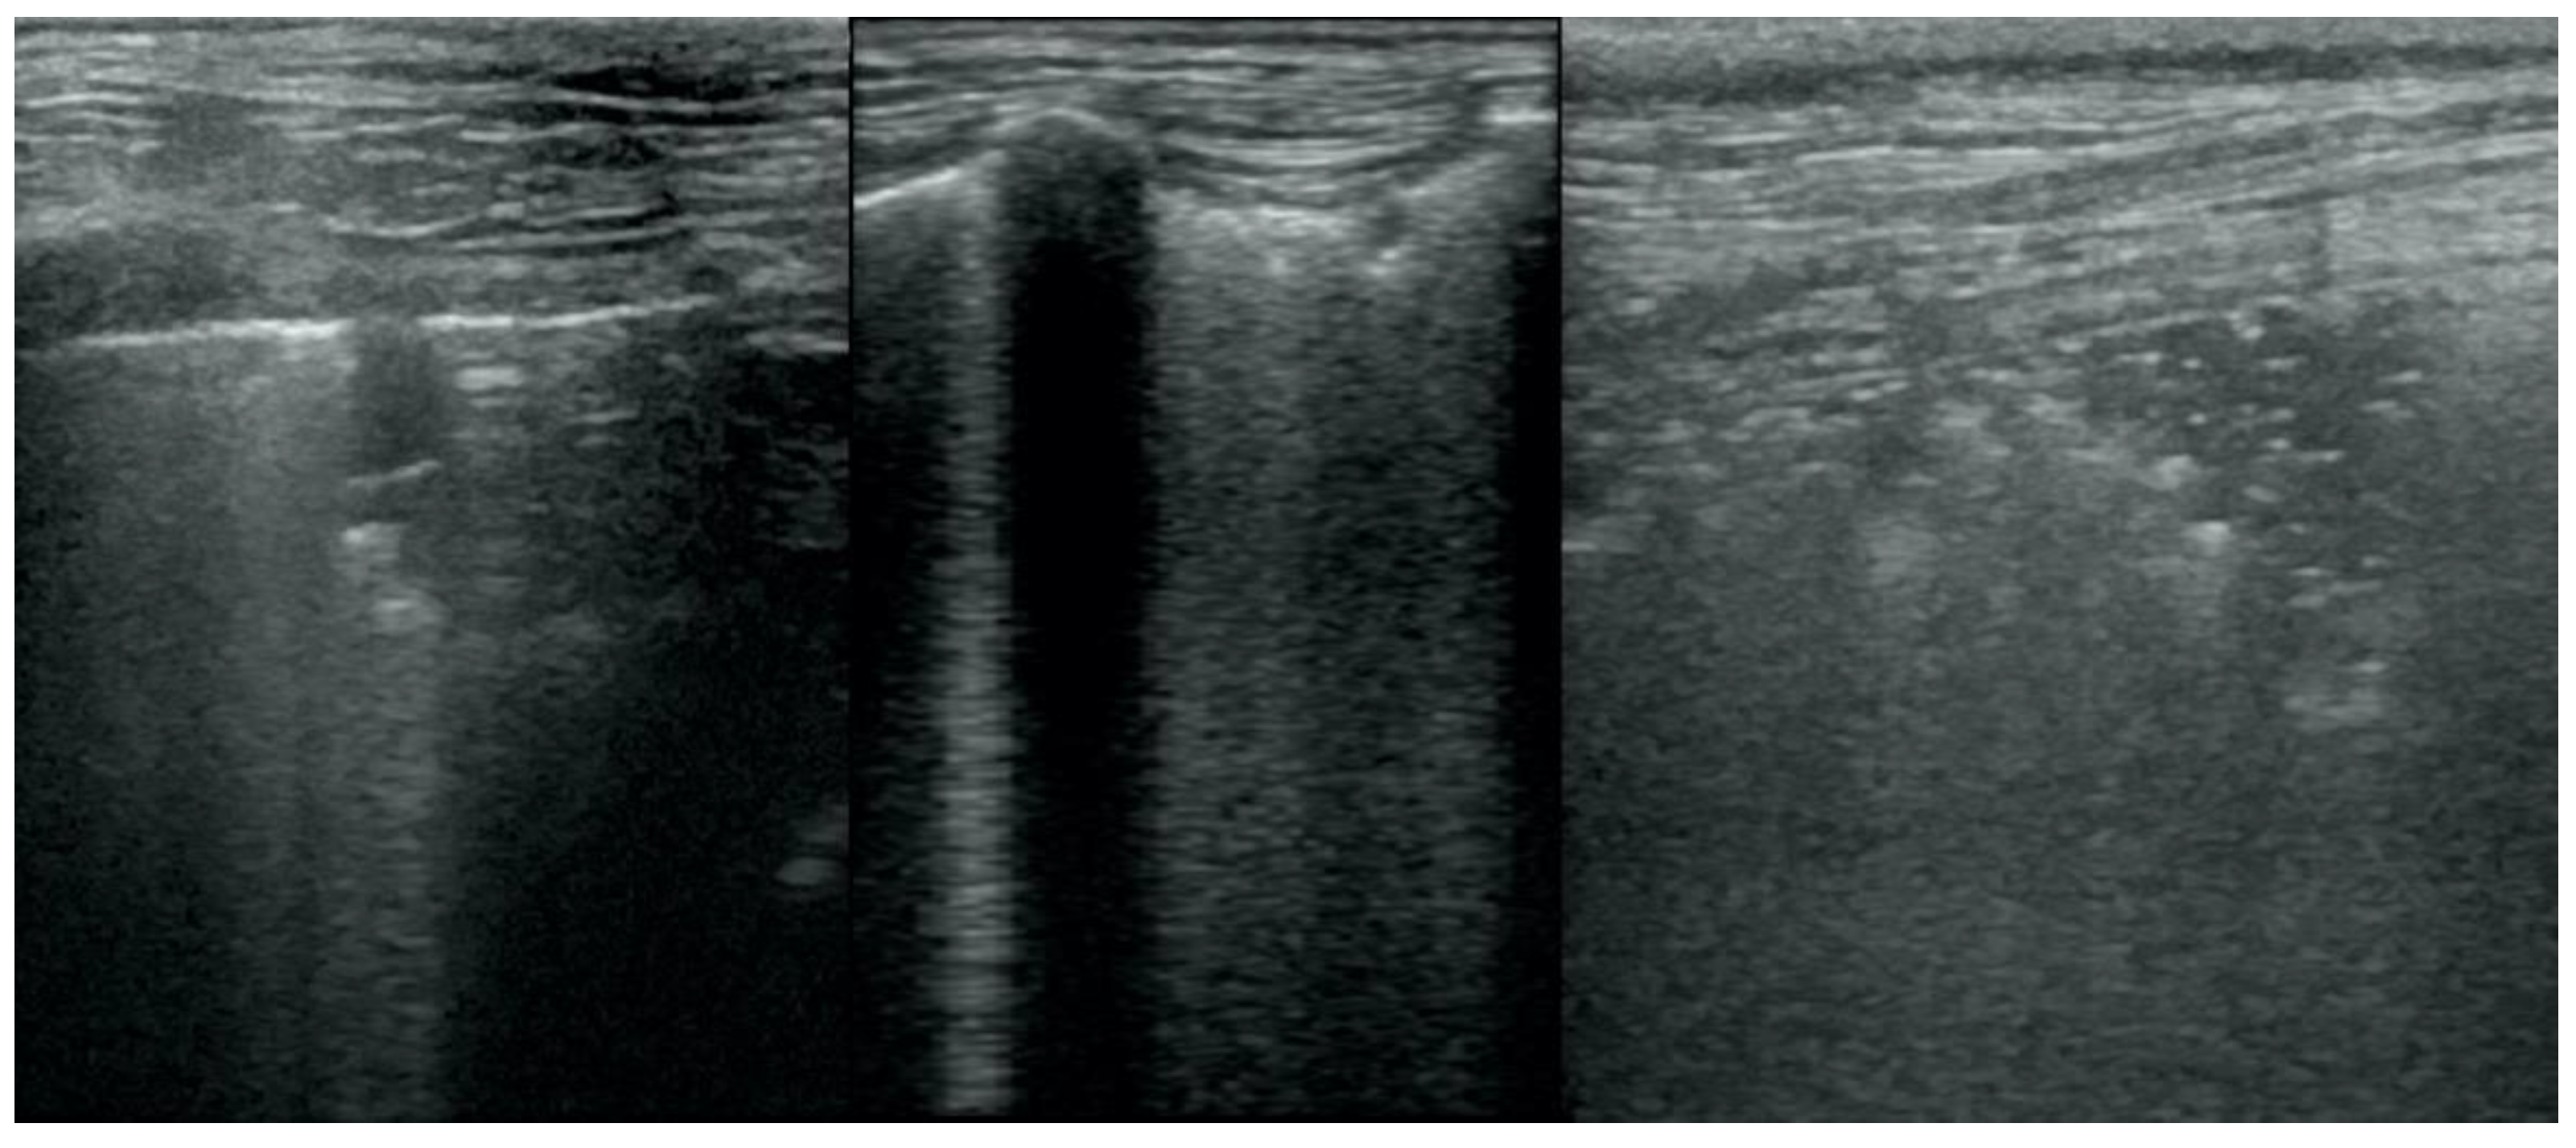

• B-lines (Figure 2);

Figure 2. Multiple B-lines.

Figure 5. Hepatization without aeration in the course of pneumonia.

Animals 12 01154 g005

Figure 6. Hepatization without aeration in the course of lung cancer.

Animals 12 01154 g006